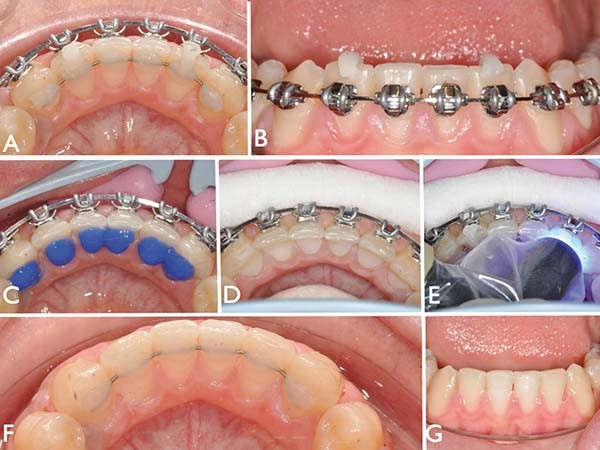

Collage en vision directe d’une contention indirecte

L’objet de cet article est de présenter une « option » avec des « nez de repositionnement », la gouttière de transfert étant supprimée. La vérification de l’adaptation parfaite du fil aux surfaces dentaires se fait en vision directe.